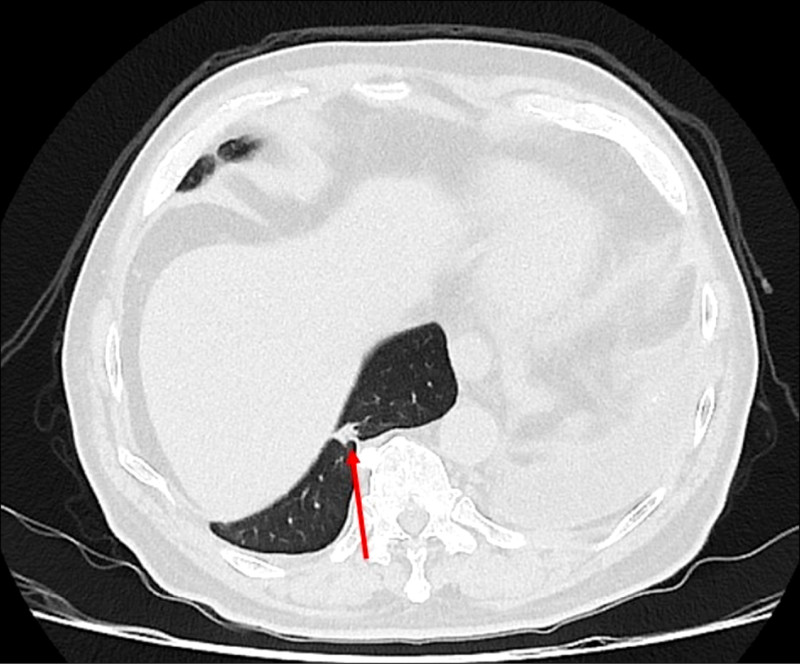

75歲吳先生因肝臟細胞癌接受治療,沒想到又發現右下肺有1顆約1.2公分的腫瘤,因疑似肺癌轉介到胸腔及心臟血管外科,醫療團隊評估後,決定進行手術切除,但因患者過去有車禍導致橫膈膜受傷,讓手術預期難度提高,決定採用健保給付的達文西機器人手術執行肺結節切除,順利切除腫瘤,並在術後第3天就出院返家休養。

廖啟耀指出,患者的橫膈膜如果和肺臟沾黏,手術空間將較為狹小,達文西機器人手術可提供穩定的操作及清晰的手術視野,外科醫師可透過穩定且精細的操作,團隊將患者的橫膈膜與肺臟分離,並完成之後的肺結節切除手術。